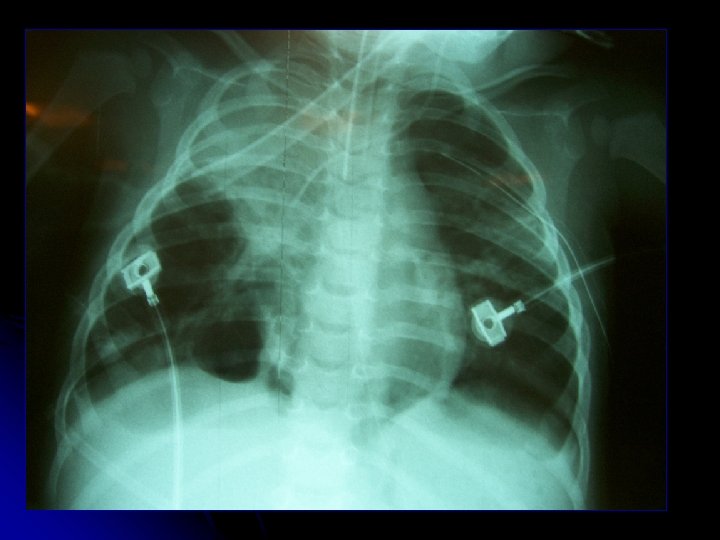

l l ♀ A. C. A. 1 a 3 m Antecedentes l l RNPT 30 sem DBP no O 2 dependiente Atresia esofágica op Cuadro actual l l 1 semana rinorrea y tos. Fiebre 4 días Hospitalización 29/12 Rápida progresión → UCIP a VM l Rx: pneumotórax a Izq. c/drenaje l Deterioro 24 hrs: Sospecha fístula broncopleural l VM: 29/10 PMVA 15 FIO 2 80 l 31/12: Traslado a VAFO l IFIs (-)

l Ingreso 31/12 l l l Saturación 83% y escape aéreo VAFO: PMVA 25, ΔP 45, FR 9 Hz; FIO 2 100% Prono Gases: PH 7, 5 PO 2 42 PCO 2 55 Pa/FIO 2 42 IO 42 Inicio empírico de sildenafil y milrinona ATB